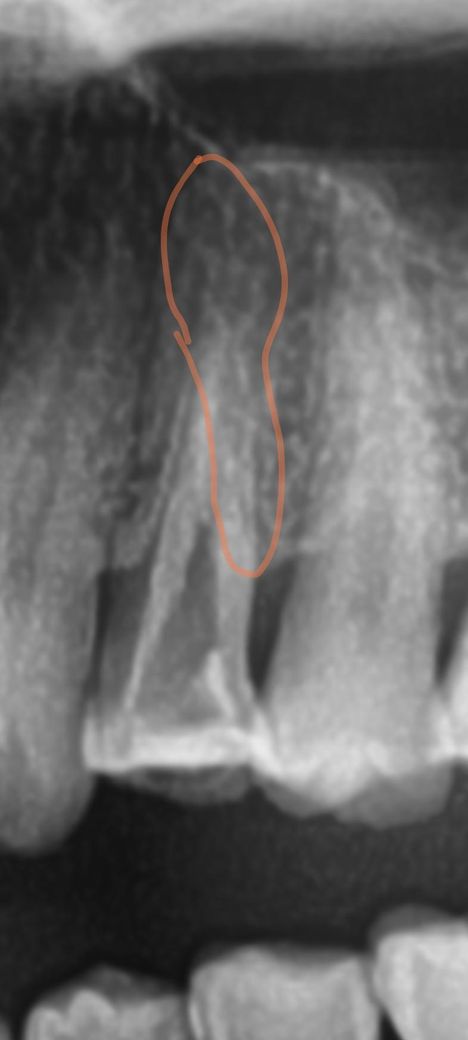

빨간색선으로 표시된부분이 금이나 충치같고 뿌리끝으로 충치나 금이 이어저서 뿌리쪽 뼈까지 녹고 염증 치근병소를 만든거 아닐까싶어요

사진상으로 보면 신경관이 많이 막혀 잇는 상태인거 같습니다 저 뿌리쪽에 신경이 제거가 되지 않는게 원인이라면 대학병원 보존과를 가보시거나 발치를 해야될것같습니다.

이미 해당 치아의 신경관 상단부는 확대가 많이 된 상태입니다. 하단부 분지부에서 놓친 신경관이 있을 수도 있고, 뿌리쪽 미세 크랙이 있을 수도 있습니다. 방사선 사진에서 표시한 게 크랙으로 보여지진 않습니다.